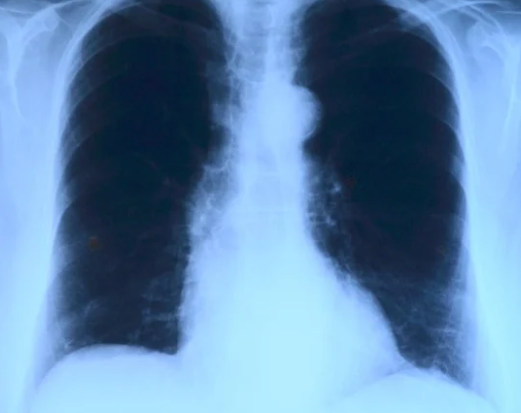

흉막에 생기는 염증으로 페렴,바이러스 감염, 결핵, 흉부외상 등의 합병증 등으로 일어나는 경우가 많습니다. 흉막염이 생기면 오한을 수반한 돌연한 고열과 호흡,기침,하품등을 수반하는 강한 흉통,식욕부진, 기침 객담의 증가등이 일어날 수있고 이때 갈비뼈 아래왼쪽에도 통증이 일어날 수있습니다.